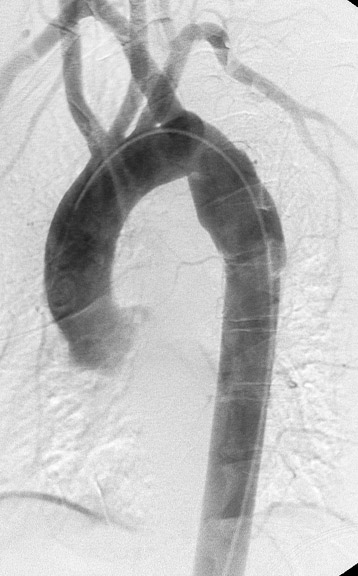

Gallery Blunt Chest Trauma Tr Aortic Injury Case 5b

Case 5b